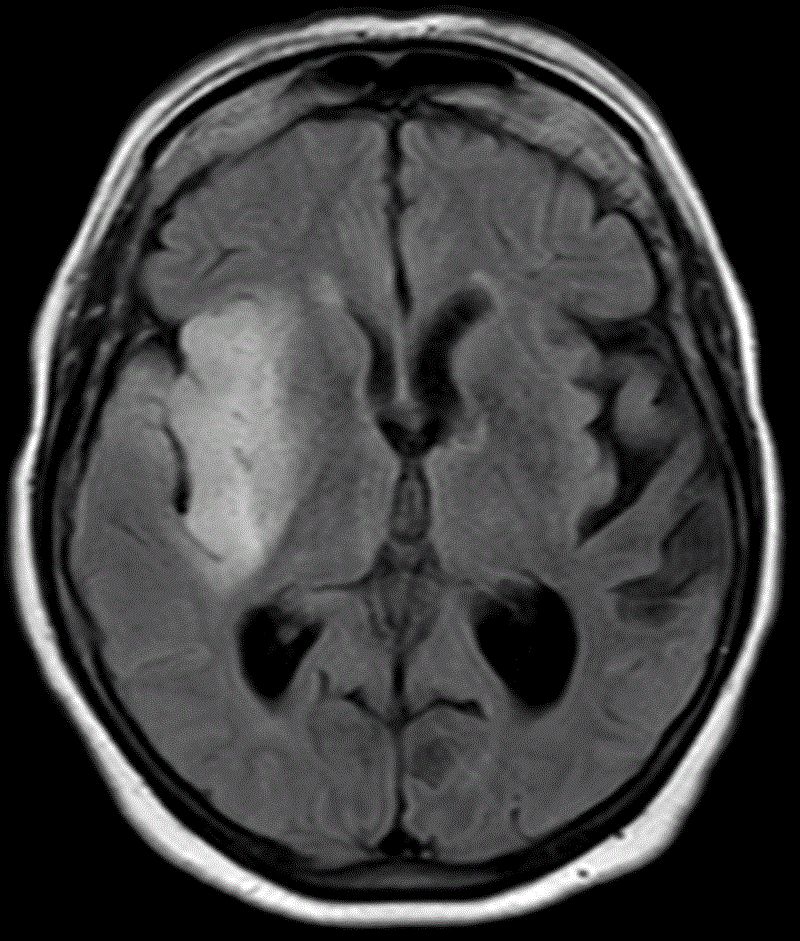

Glioblastom als Rezidiv eines Astrozytoms |

36-jähriger Mann, der vor 7 Jahres ein rechts-frontales Astrozytom Grad II mit Übergang in ein anaplastisches Astrozytom III hatte.![]() |

Jetzt Krampfanfall. Das MRT zeigt ein großes frontales Schmetterlingsgliom.![]() | |||

Die MRT-Kontrolle mit KM vor einem Jahr zeigt eine unauffällige Resektionshöhle.![]() |